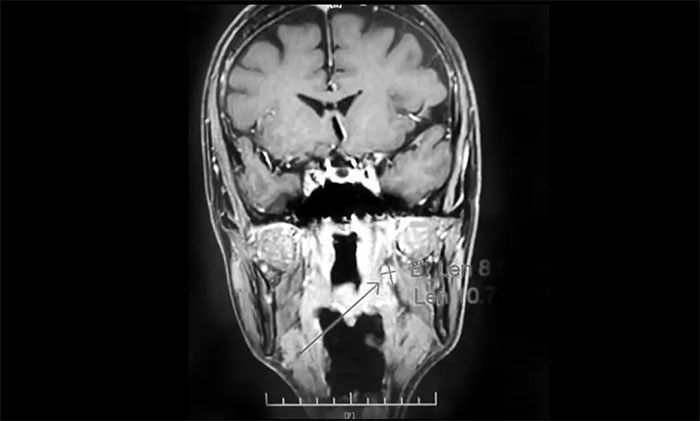

经MDT多学科会诊评估,制定以放疗为主的同步放化疗方案。治疗后复查MRI,患者左侧鼻咽部实性占位较前治疗明显减小;原左侧下颌腺区、咽旁肿大淋巴结已基本吸收好转,左颈部肿大淋巴结较前明显缩小。

▲ 放疗后复查MRI,肿瘤占位较前明显减小